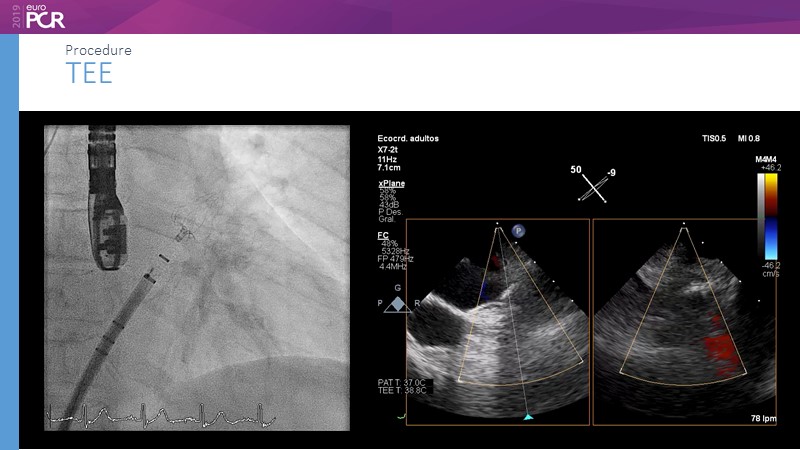

Optimising procedural outcome and safety

Previous Next